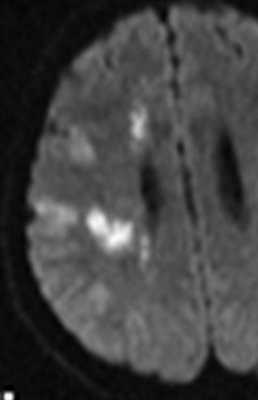

МРТ головного мозга. Аксиальная Т2-взвешенная МРТ. Кровоизлияние в мозжечок.